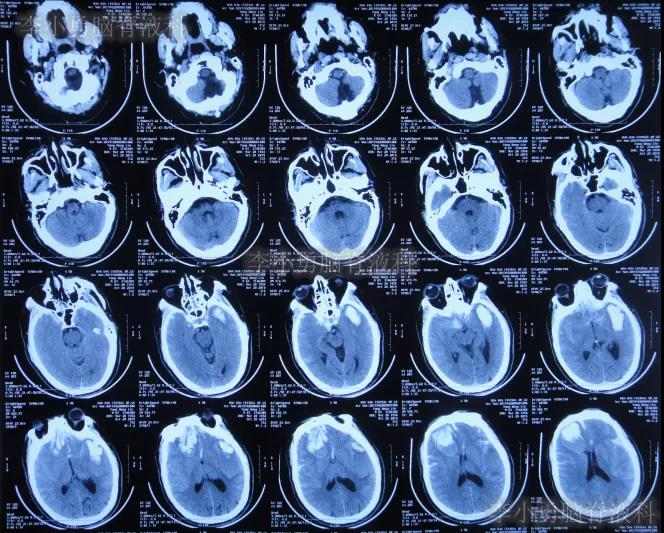

2019年10月20日患者骑电动车在马路上行驶时被大货车撞倒,当时意识清楚,只感到有些头晕,未在意就自行回家,但回家后约3-4小时出现头晕加重,并伴有恶心呕吐的症状,家人急送到当地的河北省邯郸市某医院,查头颅CT示脑出血(图-1);既往病史2015年曾因头部外伤致硬膜下血肿,进行了钻孔引流术。

图-1:2019年10月20日头颅CT

急诊进行了开颅去骨瓣血肿清除术,术后次日查头颅CT示去骨瓣术后(图-2)。

图-2:2019年10月21日头颅CT